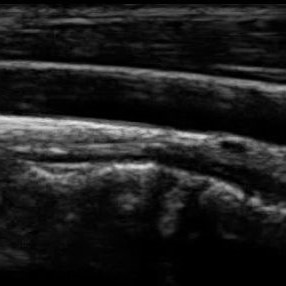

To evaluate the performance in terms of OOD detection, three different OOD test data sets were used: MNIST (test set), CorruptPOCUS and CCA. The MNIST test set consists of 10 000 images of handwritten digits [14]. The CorruptPOCUS and CCA data sets were chosen to resemble realistic OOD data, such as ultrasound images containing artefacts. The CorruptPOCUS data set resembles POCUS images of poor quality and was generated by distorting the POCUS test set by adding dark areas, blur and noise. The CCA data set contains 84 ultrasound images capturing the common carotid artery [15], i.e., non-breast US images. An example of a real POCUS image of poor quality as well as examples of the three OOD data sets can be seen in Fig. 2.